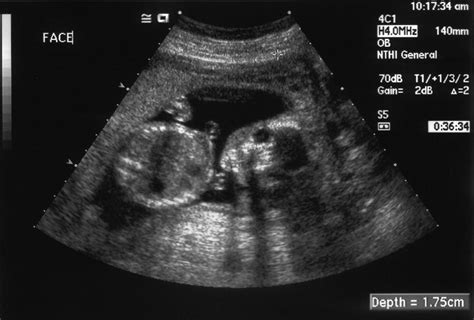

- Ultrazvukové vyšetrenie: Slúži na posúdenie rastu plodu, jeho hmotnosti, objemu plodovej vody a na vizuálnu kontrolu štruktúry a hrúbky placenty.

- Flowmetria: Ultrazvukové vyšetrenie prietokov krvi v pupočníkových cievach a iných cievach fetoplacentárnej jednotky, ktoré hodnotí funkciu placenty a jej schopnosť dodávať kyslík a živiny plodu.

V 36. týždni tehotenstva sa často vykonáva ultrazvuková flowmetria, ktorá detailne posudzuje funkciu fetoplacentárnej jednotky.